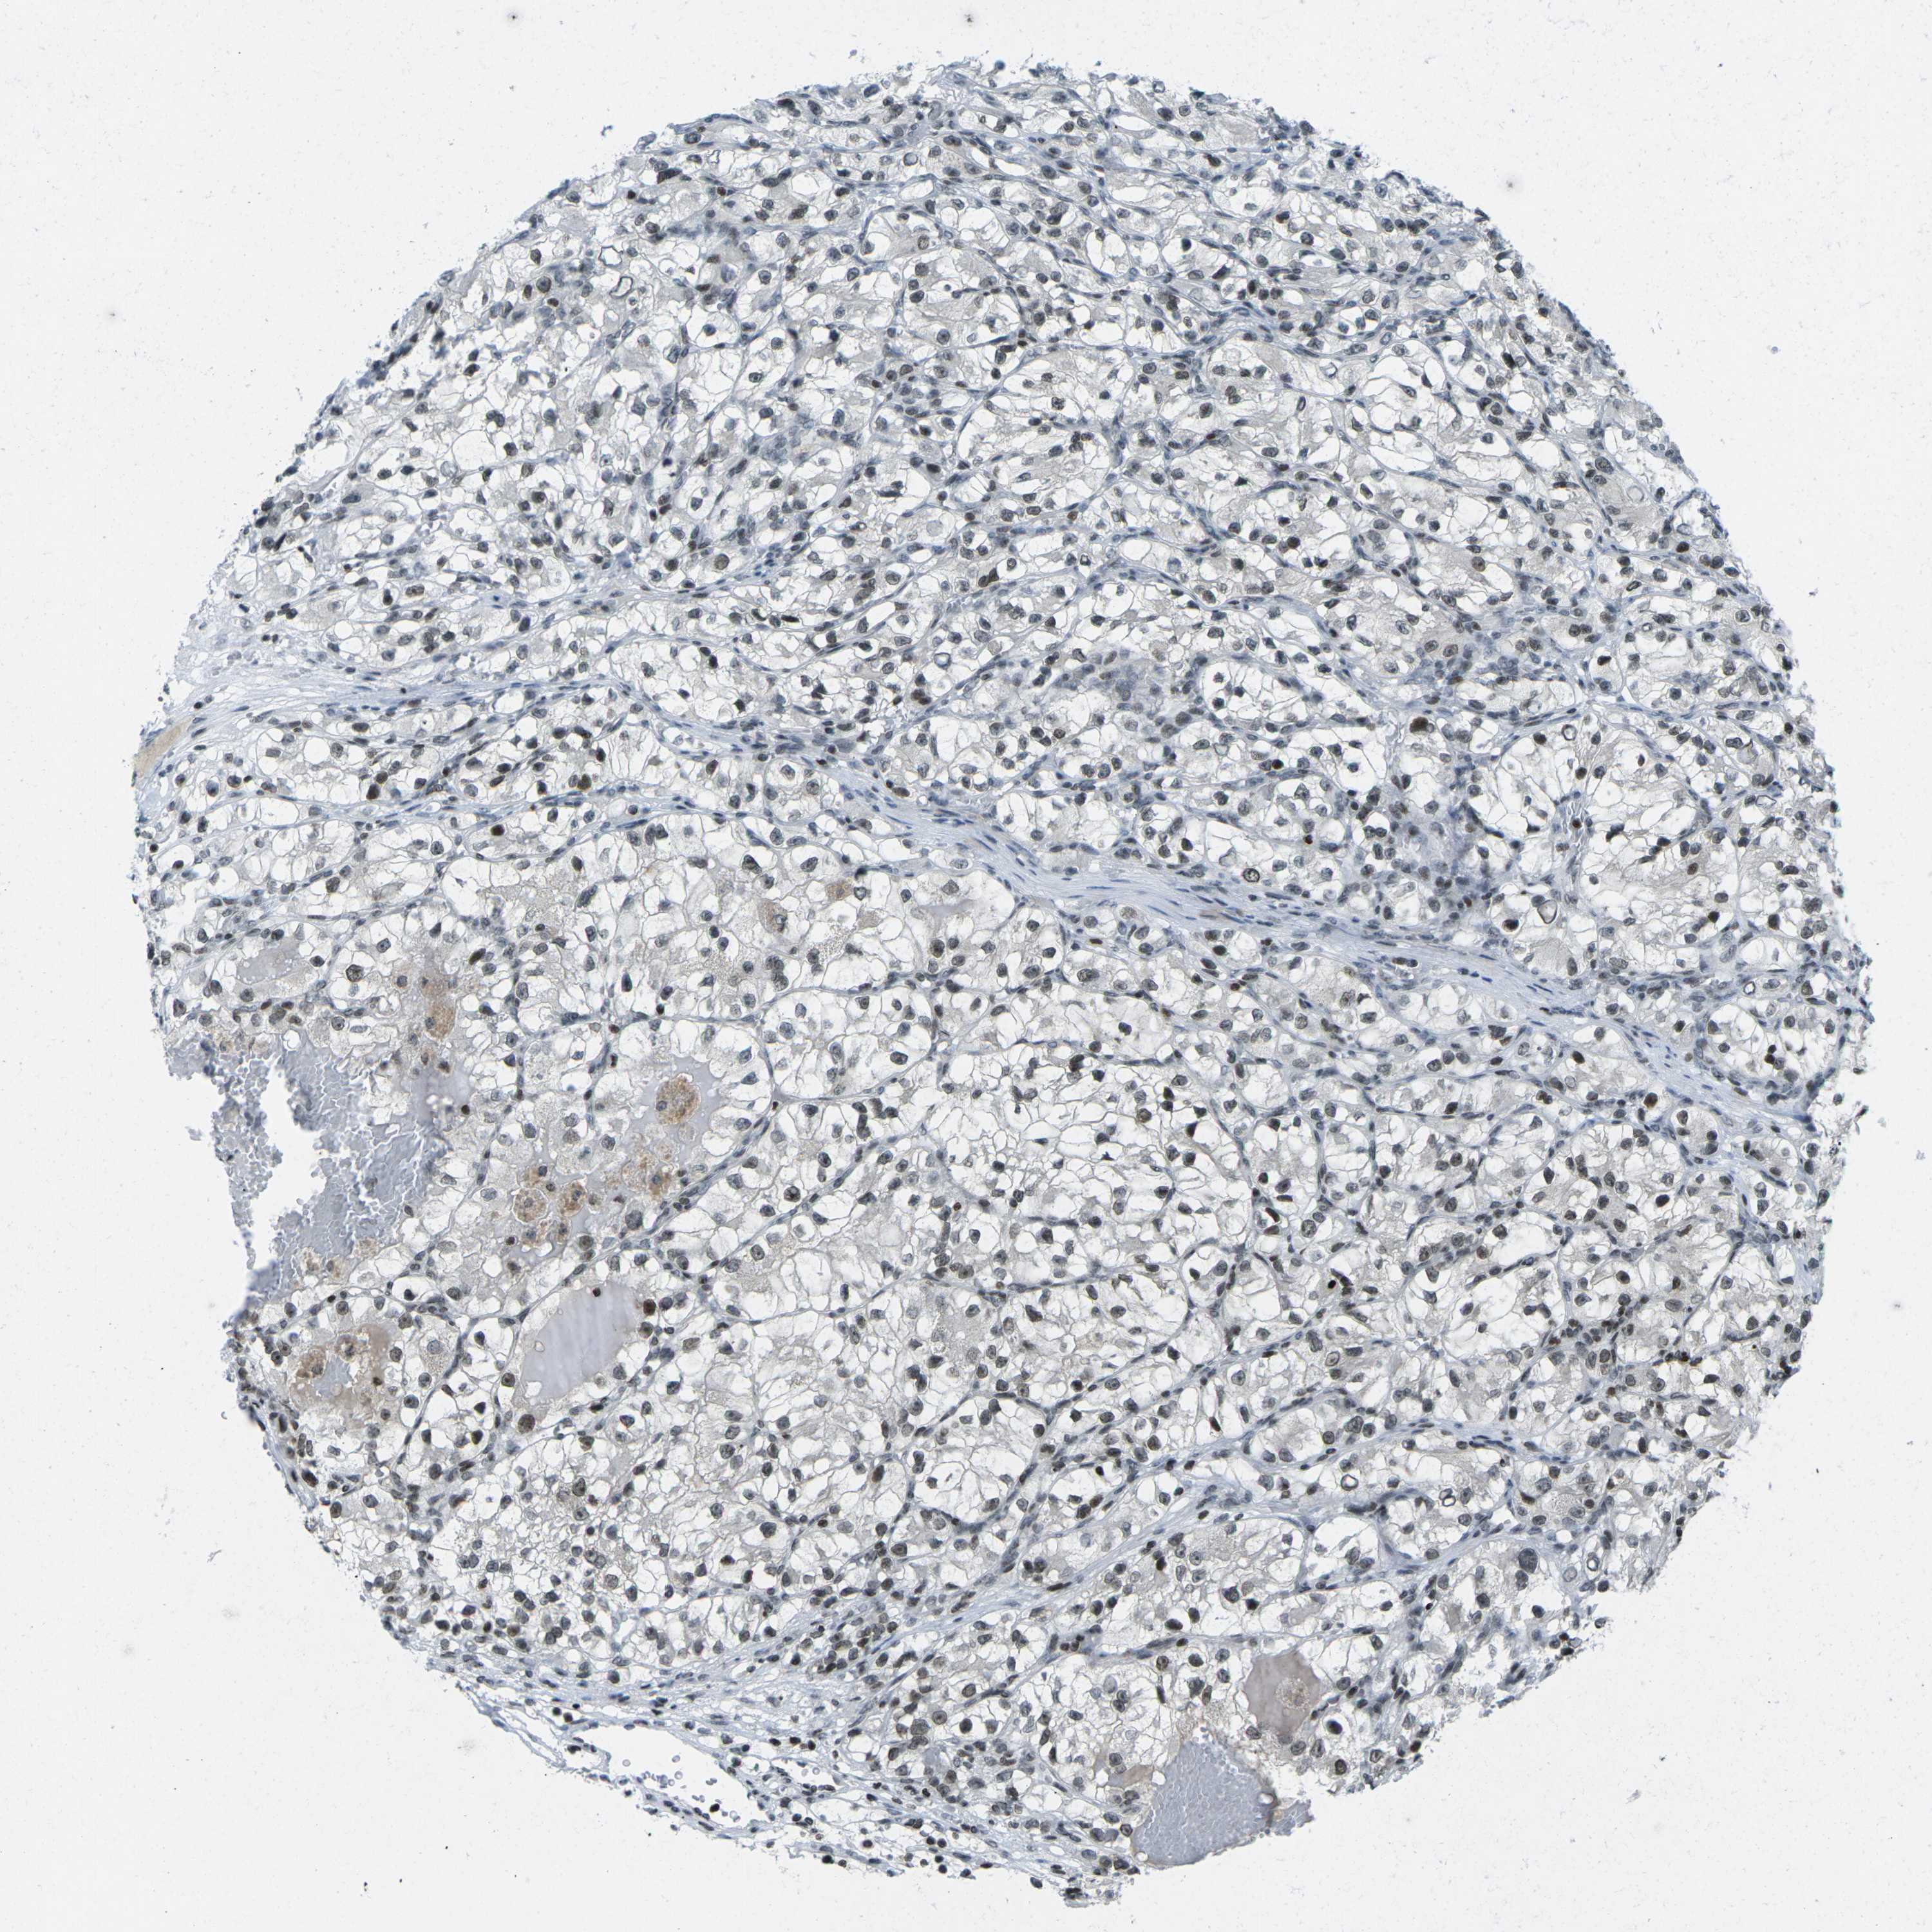

KIDNEY RENAL CLEAR CELL CARCINOMA (VALIDATION) - Interactive survival scatter ploti

The Survival Scatter plot shows the clinical status (i.e. dead or alive) for all individuals in the patient cohort, based on the same data that underlies the corresponding Kaplan-Meier plots. Patients that are alive at last time for follow-up are shown in blue and patients who have died during the study are shown in red.

The x-axis shows the expression levels (FPKM) of the investigated gene in the tumor tissue at the time of diagnosis. The y-axis shows the follow-up time after diagnosis (years). Both axes are complimented with kernel density curves demonstrating the data density over the axes. The top density plot shows the expression levels (FPKM) distribution among dead (red) and alive patients (blue). The right density plot shows the data density of the survived years of dead patients with high and low expression levels respectively, stratified using the cutoff indicated by the vertical dashed line through the Survival Scatter plot. This cutoff is automatically defined based on the FPKM cutoff that minimizes the p-score. The cutoff can be changed by dragging the vertical line or by entering a cutoff value in the square labeled "Current cut-off".

Under the Survival Scatter plot the p-score landscape (black curve; left axis) is shown together with dead median separation (red curve; right axis). Dead median separation is the difference in median mRNA expression between patients who have died with high and low expression, respectively. It is calculated as follows: median FPKM expression of dead patients with high expression - median FPKM expression of dead patients with low expression. This is intended to aid the user in visually exploring custom cutoffs and the associated p-scores and dead median separation.

Individual patient data is displayed and can be filtered by clicking on one or more of the category buttons on the top of the page. Categories describing expression level and patient information include: high, low, alive, dead, female, male and tumor stages. The scale of the x-axis can be toggled between linear and log-scale by clicking on the "x log" button. Mouse-over function shows TCGA ID, patient information and mRNA expression (FPKM) for each patient.

& Survival analysisi

Kaplan-Meier plots summarize results from analysis of correlation between mRNA expression level and patient survival. Patients were divided based on level of expression into one of the two groups "low" (under cut off) or "high" (over cut off). X-axis shows time for survival (years) and y-axis shows the probability of survival, where 1.0 corresponds to 100 percent.

EME1 is potential prognostic, high expression is unfavorable in Kidney Renal Clear Cell Carcinoma (validation)

: 1.22

Average pTPM 1.1

Number of samples 100